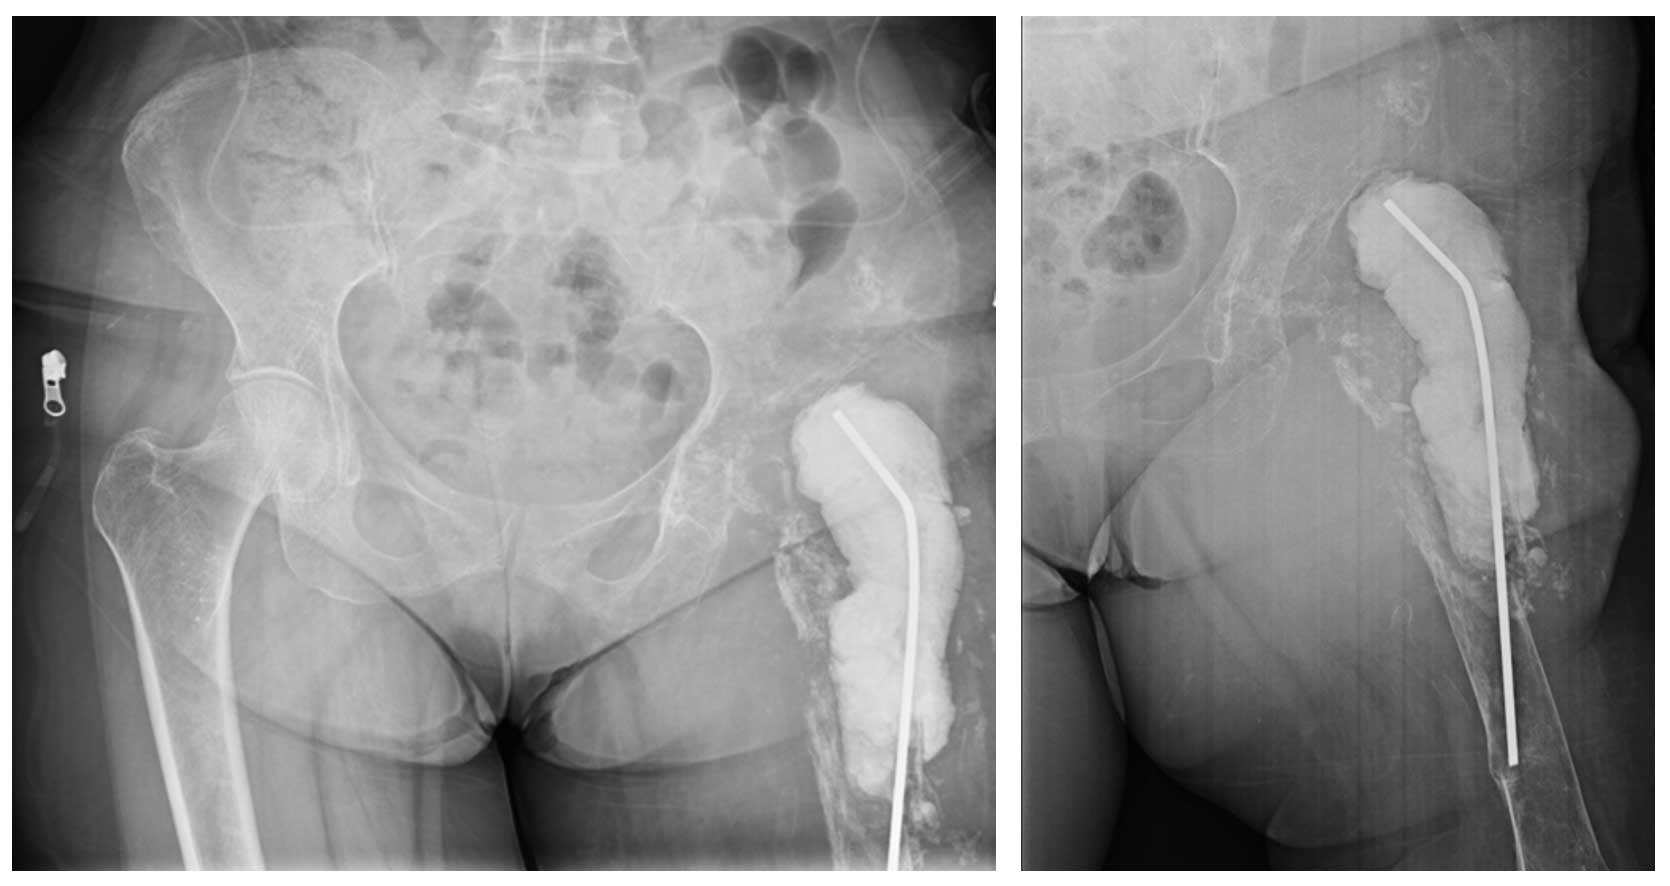

Ameliyat Sonrası: Röntgende proksimal femur rezkesiyonu ve internal hemipelvektomi sonrası antibiyotikli spacer uygulanımı görülmekte.